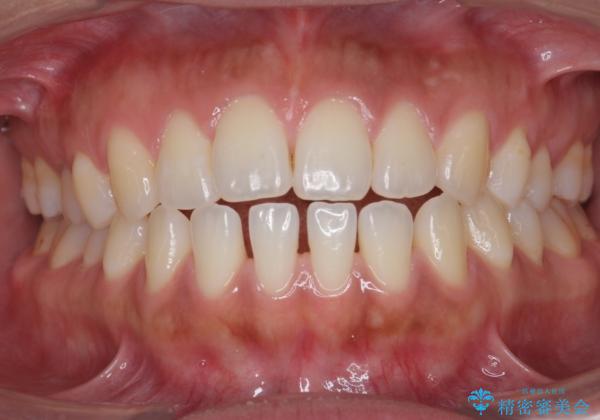

受け口、すきっ歯を インビザラインで モニター治療

- 前歯のすき間と受け口を気にして来院。

マウスピースでしっかり閉じています。

下の前歯を後方に移動するため、ゴムを上下のマウスピースにかけてもらいました。